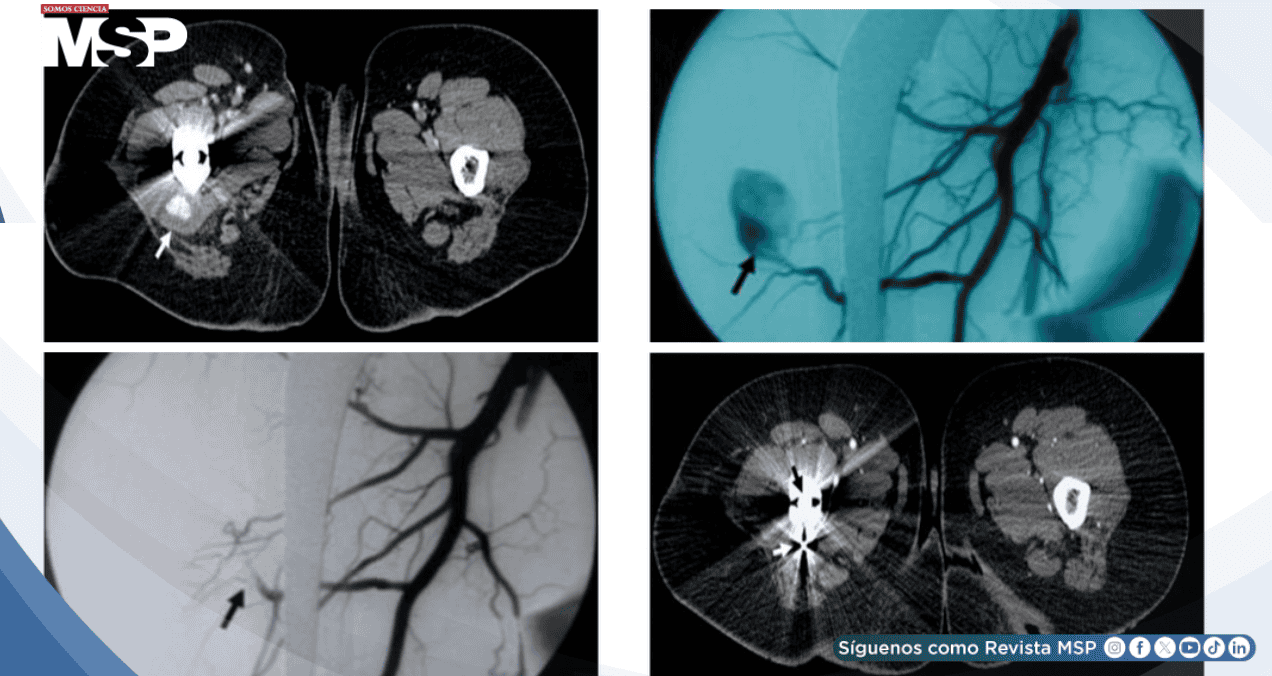

La tomografía computarizada posterior precisó las características de la lesión: un pseudoaneurisma de 14 × 22 mm que se originaba específicamente en una rama perforante distal de la arteria femoral profunda derecha.

Se realizó una arteriografía mediante acceso retrógrado por la arteria femoral izquierda, confirmando la presencia y características del pseudoaneurisma.

El procedimiento terapéutico consistió en el cateterismo selectivo de la rama perforante comprometida utilizando un microcatéter especializado. Se logró la embolización exitosa mediante la colocación estratégica de bobinas de platino de 2 y 3 mm, posicionadas tanto distal como proximalmente al cuello del pseudoaneurisma. La angiografía de control inmediata demostró la exclusión completa de la lesión, sin evidencia de flujo residual hacia el saco aneurismático.